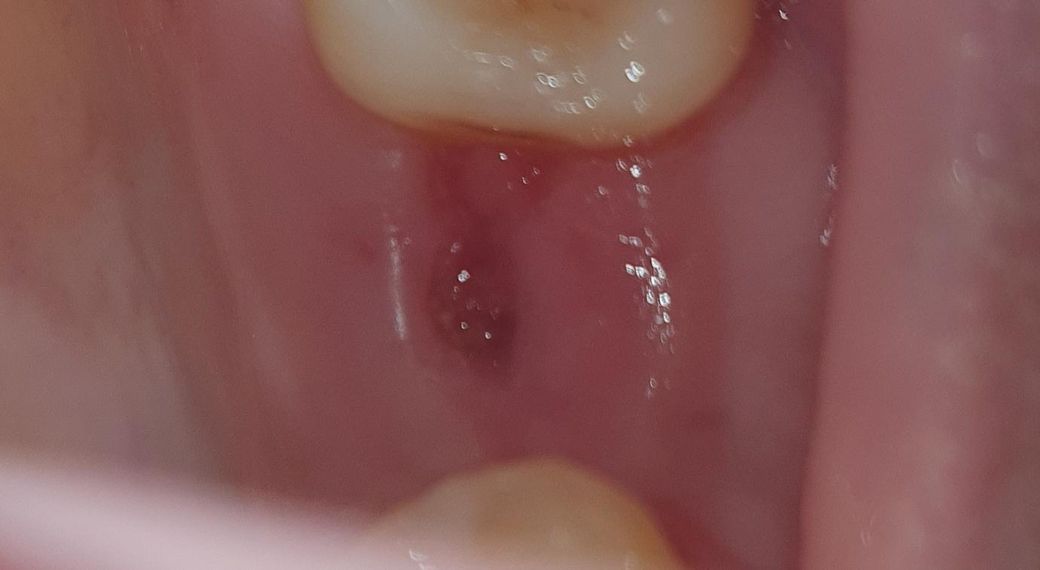

임플란트 픽스쳐 식립한지 17일정도 됐는데

잇몸조직이 부족해서 봉합은 안했었고

오늘보니 사진처럼 저렇게 되어있는데

괜찮은건가요? 아프거나하진 않은데

구멍이 저렇게 생길지 몰랐어서 걱정되서요

잇몸이 수술 부위 주위로 수축했는데 저정도면 잇몸이 차오르면서 자연스럽게 치유됩니다 수술 후 2달 정도는 있어야 모양이 잡힙니다